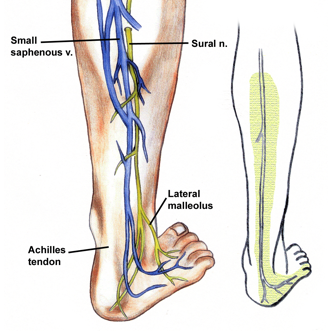

origin course and distribution of sural nerve

O formed by the union of the cutaneous banches from the tibial and common fibular nerves

C descends between heads of gastroc; becomes superficial at middle of leg; descends with small saphenous vein; passes inferior to lateral malleoulus to lateral side of foot